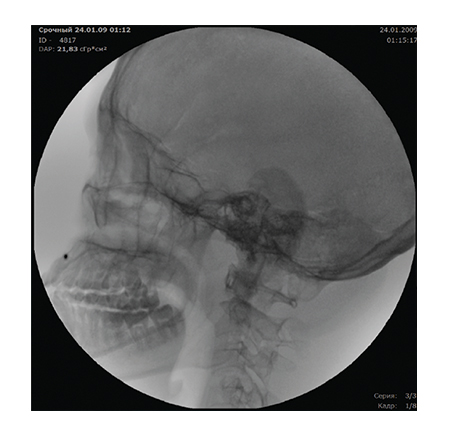

The high image quality provided by mobile C-arm systems is achieved due to a digital imaging system, which allows seeing even the smallest defects and pathologies. A mobile C-arm system model with a flat panel detector provides for imaging of even the smallest vessels. The modes of pulsed fluoroscopy, lowered dose fluoroscopy, and special quality fluoroscopy in combination with the wide APR program range, which considers the patient’s age and the body build, allows obtaining a high-quality image with the minimum exposure dose.

Thanks to an effective cooling system of the X-ray tube assembly, the system provides for a long period of X-ray control, which determines the use of the system for a wide range of diagnostic and medical-surgical manipulations on the heart and vessels. The subtraction angiography mode, the vascular package, the routing, and mask selection option create the necessary conditions for successful use of the system in coronary angiography, angiography, and control of electrophysiology procedures.